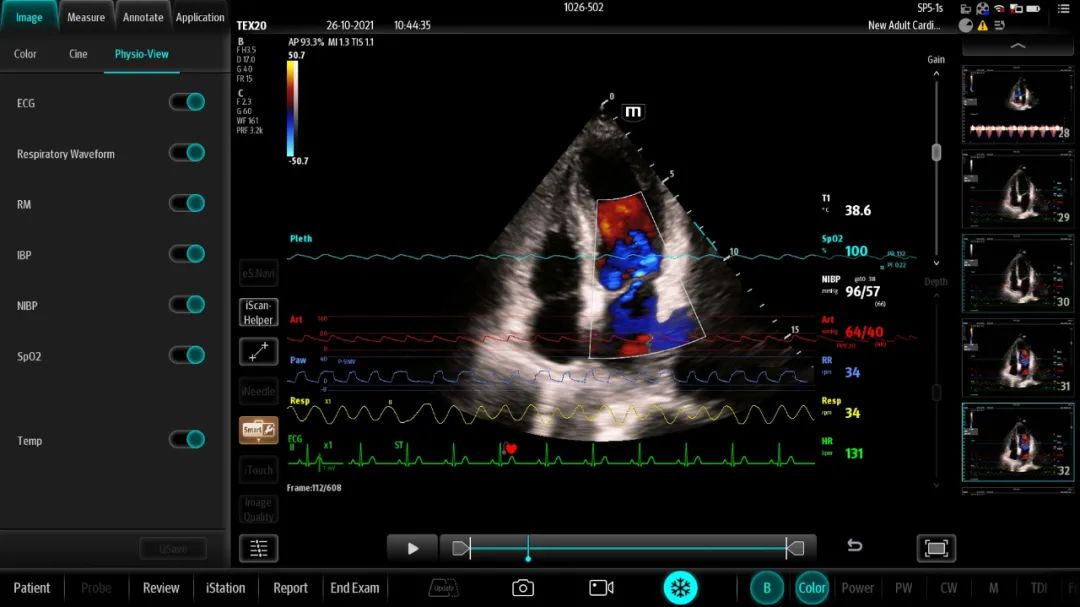

智监护+系统将监护仪、呼吸机等数据/波形有机“融入”超声影像界面,同屏同步展现动态变化。比如结合ECG及IBP波形呈现心脏电活动-机械舒缩-外周血压变化的完整生理过程,为状态评估提供有力支持。